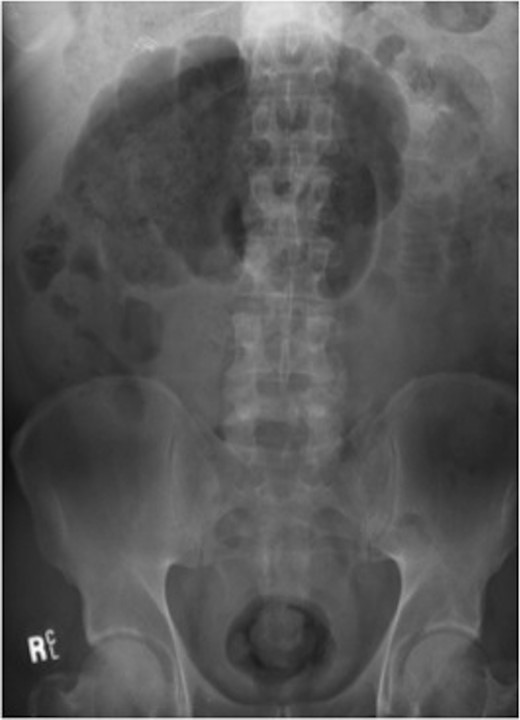

Haemoglobin was 14.9 g/dl and the white cell count (WCC) was 9 × 109/l. Other remarkable laboratory tests included a C-reactive protein (CRP) of 15 mg/l. Urinalysis was normal. The plain X-ray abdomen (AXR) (Fig. 1) revealed dilatation of a focal segment of large bowel with mildly dilated small bowel. Computed tomography (CT scan) of his abdomen reported that the gas-filled viscus is likely to represent the caecum (Fig. 2).

Plain AXR (Case 1) revealed dilatation of a focal segment of a large bowel with a mildly dilated small bowel.